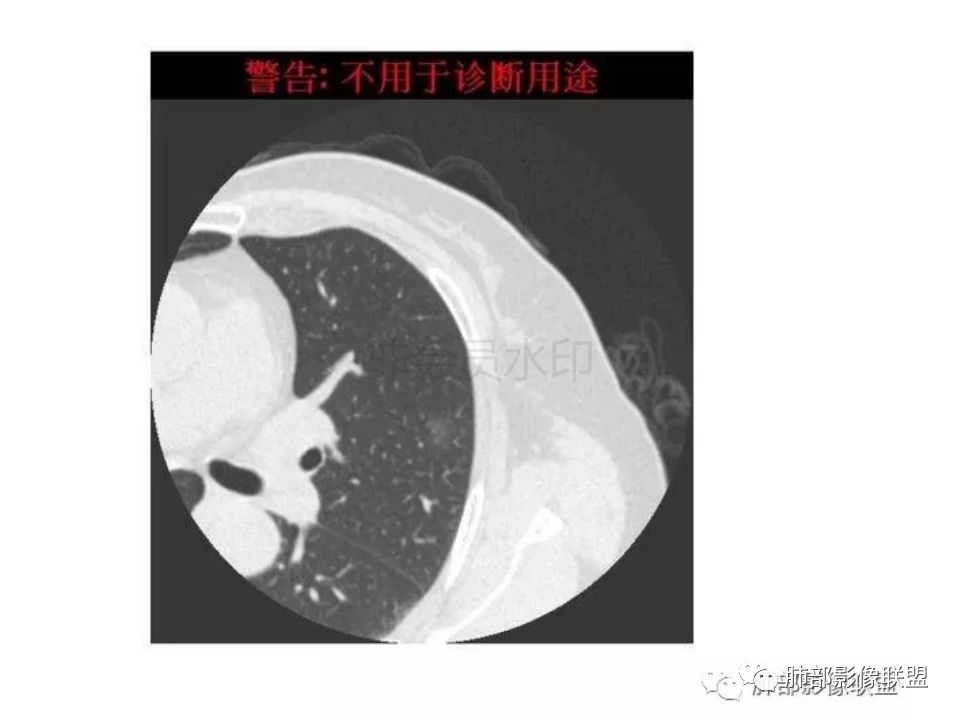

三生石上:支气管有截断,周围有晕,有空泡,腺癌?毛勤香:左肺下叶近胸膜下结节,周围磨玻璃影,边界似稍模糊,局部细支气管截断,实性区和磨玻璃区分界突然,隐约细毛刺,首先考虑感染性,隐球菌?待排腺癌MIA伴肺泡塌陷可能。常规治疗后复查。Coke with ice:IACM-Imaging :孤立胸膜下结节,其内见小泡,周围模糊的晕,晕中软毛刺,近端与血管相连,血管自然通过,气管进入结节内部一半,猜个隐球吧。第二腺癌,建议复查。田园晚风:考虑腺癌紫气东来:左肺上叶,磨玻璃实性毛刺,空泡,支气管截断,腺癌雪颜:左肺上叶结节状密度增高影,周围有晕,感觉周围模糊,有血管进入,里面有空泡征,隐约看到里面有支气管穿过,考虑炎性,隐球菌感染?腺癌待排THINKER:上叶尖后,SPN,有晕,软毛刺,无胸膜凹陷,分叶丶收缩不明显,支气管进入,远端阻塞,首选肉芽肿,PC或炎性结节,有一支血管滋养,鉴别腺癌,增殖性结核结节不支持期:左上肺结节周围有晕 晕中见细软毛刺 首先考虑隐球菌一米阳光:左肺上叶磨玻璃影,空泡,周围毛刺,月牙铲,支气管通过,周围有晕,考虑腺癌我的FY:毛刺,小空泡,磨玻璃考虑恶性崔少钢:小病灶,内有支气管,空泡征,实变不规则,放大了,感觉晕有点偏清,考虑恶性。小病灶里面有支气管是值得高度怀疑的。没有病史。彭君:左肺上叶舌段结节 周围晕模糊 内小支气管扩张 近端与血管相连 自然通过 首先考虑炎性 隐球菌?边缘月牙铲 腺癌待鉴别徐婕:左上肺结节周围有晕 ,晕中见细软毛刺 ,晕边界不太清,先考虑隐球菌张帅:左肺上叶尖后段实性病灶,以细支气管为中心,周围呈毛玻璃样影,并可见密集分布毛刺,内可见支气管征,支气管呈壁呈结节样改变,病灶周围可见血管增粗。考虑 淋巴瘤?鉴别隐球。张延军:混合型磨玻璃结节,伴毛刺,支气管截断,空泡,考虑浸润性腺癌,建议抗炎治疗后复查XGQ:支持隐球春秋:结节伴晕征,晕中毛刺,相邻小支气管近端进入,远端阻塞,近端血管相连,首先考虑隐球菌王秀仙:左肺上叶混合型磨玻璃结节,支气管截断,空泡,有毛刺,考虑浸润性腺癌,建议抗炎治疗后复查玫:左肺上叶磨玻璃结节影,薄扫见长短不一毛刺,有空泡,病灶边缘见晕征,考虑小腺癌可能,不除外炎性结节。zyf:左肺下叶近胸膜下结节,周围有晕,细软毛刺,有支气管进入,实性区和磨玻璃区分界明显,首先考虑感染性,隐球菌?查隐球菌荚膜抗原!RockJ-ason:考虑隐球采莲:左上肺靠近胸膜下实性结节影,边缘模糊,周围有晕及晕中毛刺,支气管进入通畅,有小空泡。考虑炎性病变,隐球可能性大。鉴别结核。Harvey:左肺下叶舌部小结节,边缘见磨玻璃影,边界欠清,内见支气管、管壁不光整,偏向恶性。鉴别隐球菌lmg:左肺上叶混合小结节,有晕,边界模糊,有有小毛刺。考虑炎性病变,隐球收选。AIS并肺泡塌陷带排。山河:倾向腺癌红日东升:GGO边界似清非清,内部好像不是小空泡,是小支气管腔,倾向炎性病变,常规抗炎复查除外腺癌,尤其粘液腺癌。

隐球菌感染孤立病灶与肺腺癌结节在影像上有时难分彼此,尽管隐球菌胸膜下更常见。

1.隐球菌病灶往往是实性密度结节为主伴周边边界不清楚的晕,有时可见晕内细软毛刺。

微浸润腺癌常常是磨玻璃密度为主的结节,边界比较清楚,并似乎有弧线形小叶间隔阻挡的痕迹。

实性结节的腺癌则很少有磨玻璃晕,往往会有粗短的硬毛刺。

4.隐球菌病灶增强扫描可轻度强化。既不同于结核灶的几乎不强化,也不同于肺腺癌的明显强化。

该患者实性成分为主,可惜未提供增强扫描图像。